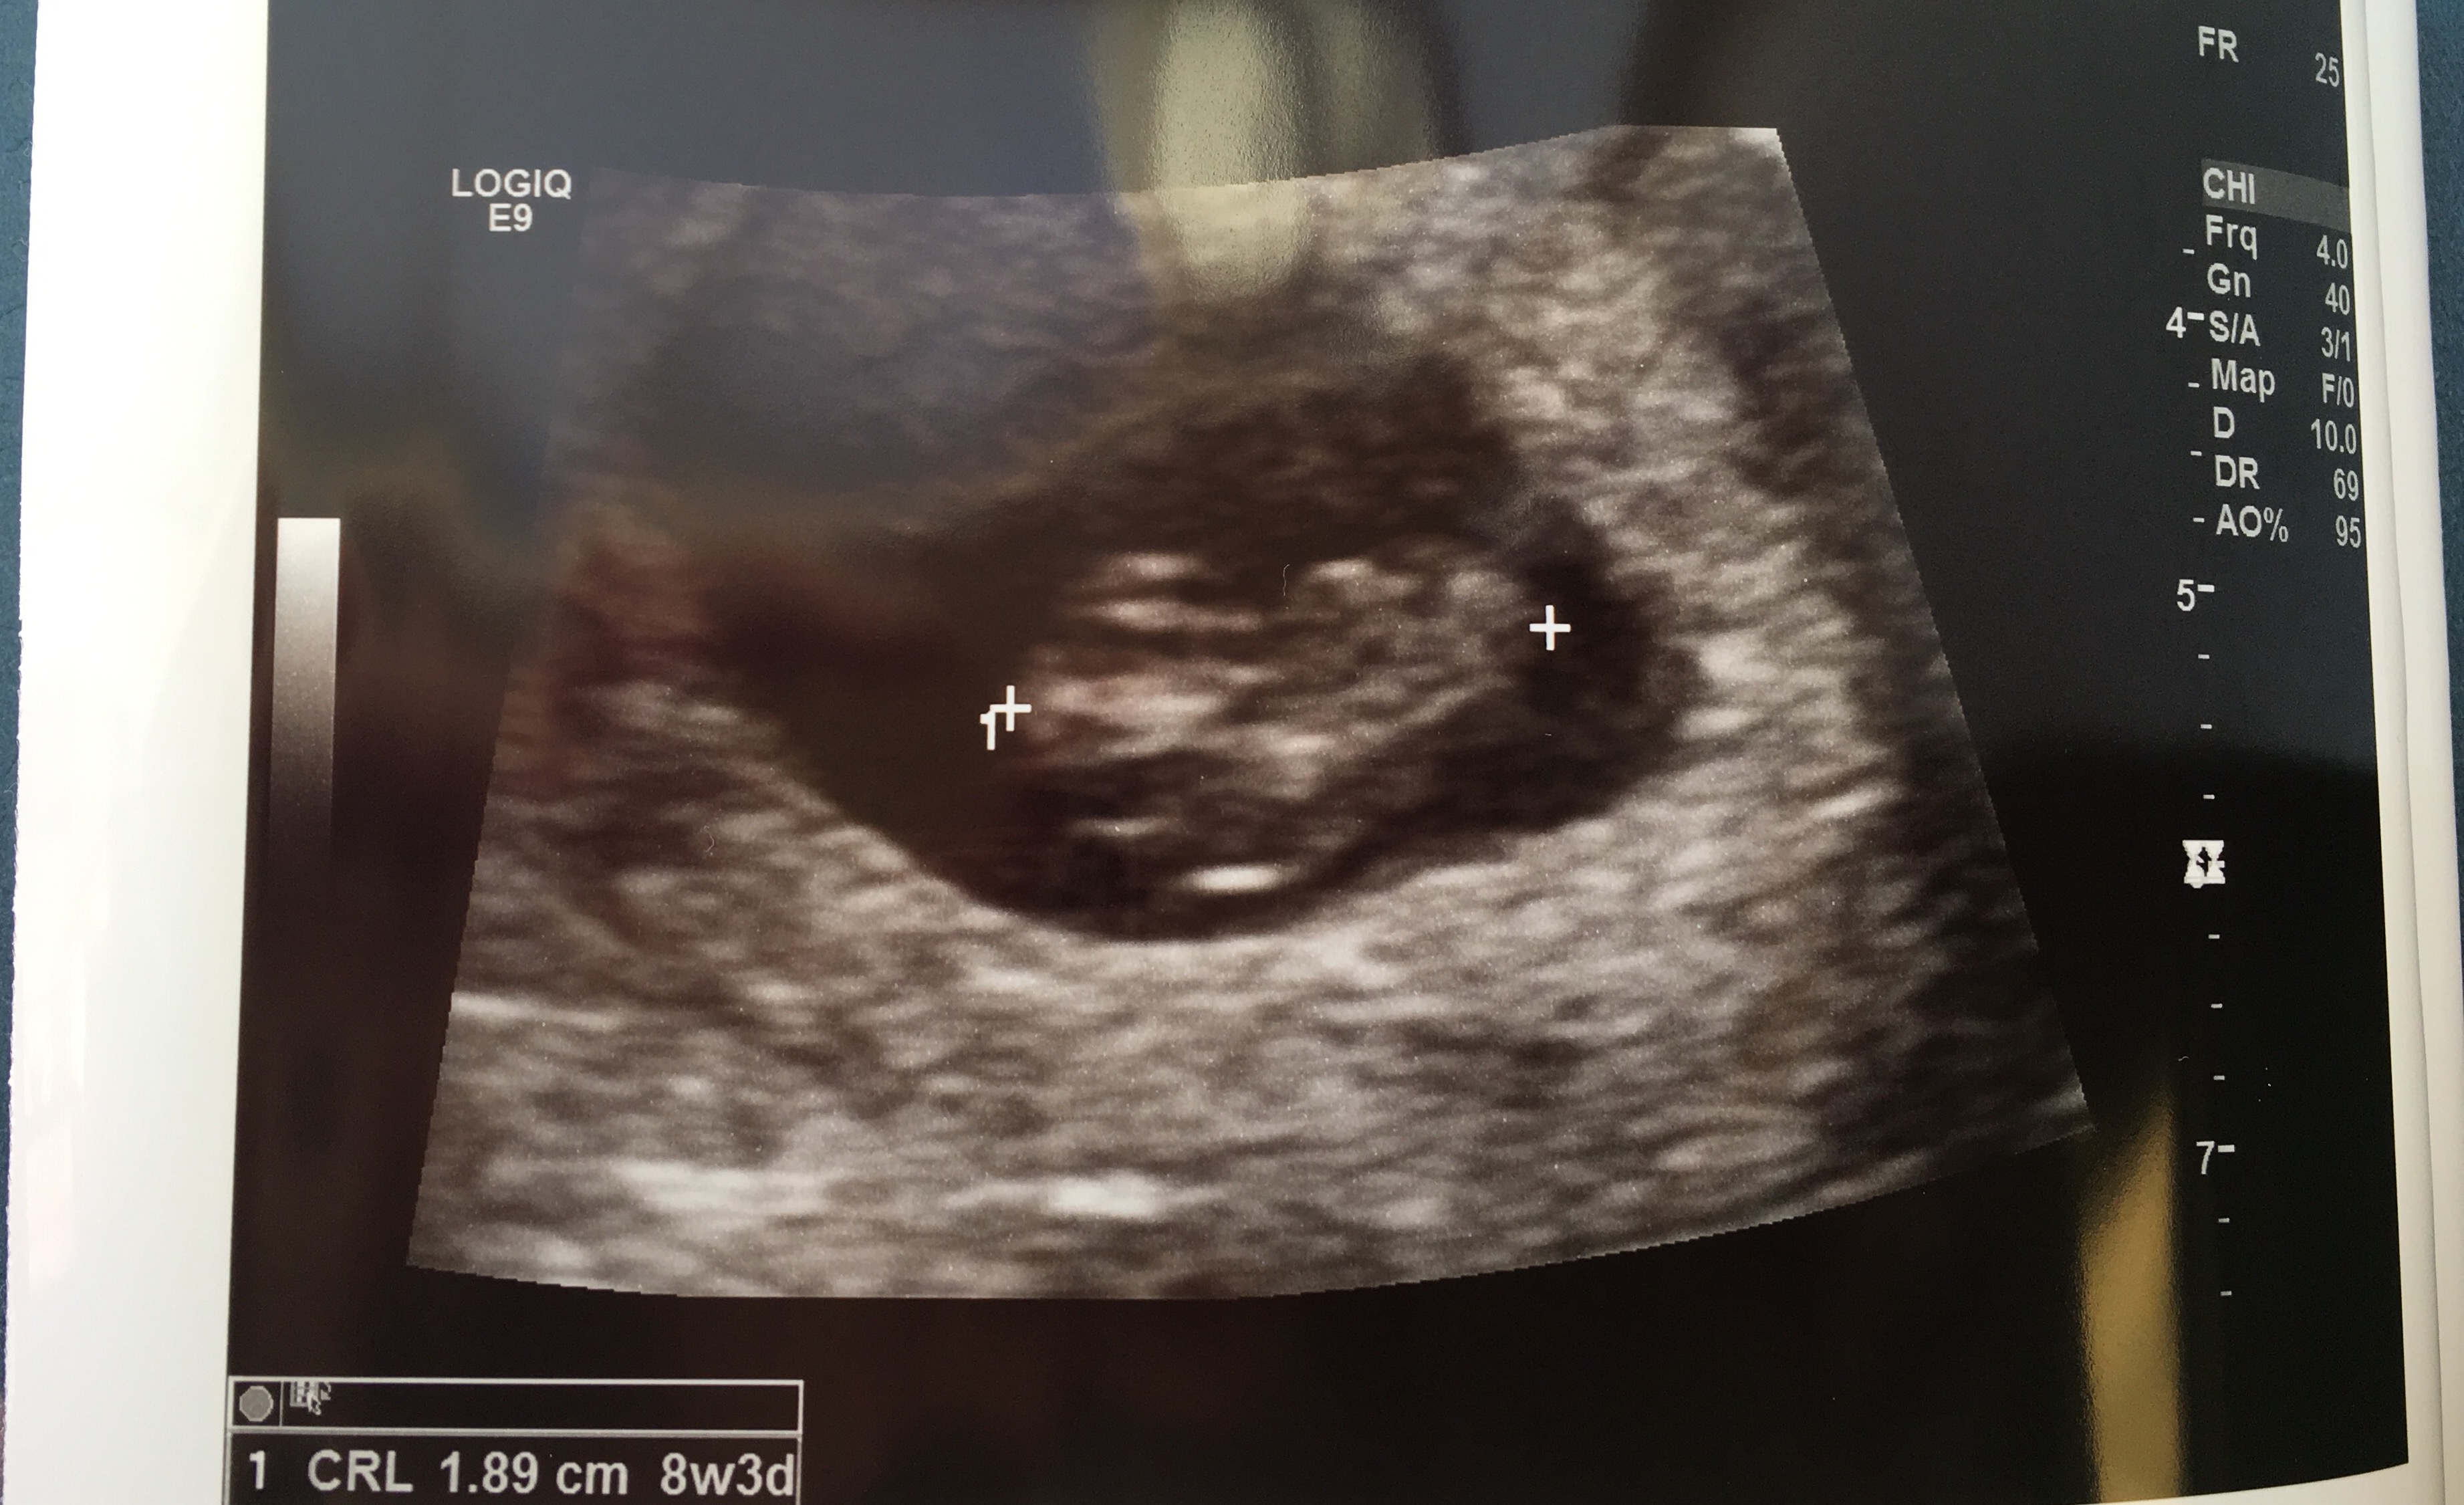

Was measuring at 8w3d instead of 8w6d based on LMP but they are keeping me at the latter with the original due date for now because of margin of error. So relieved.